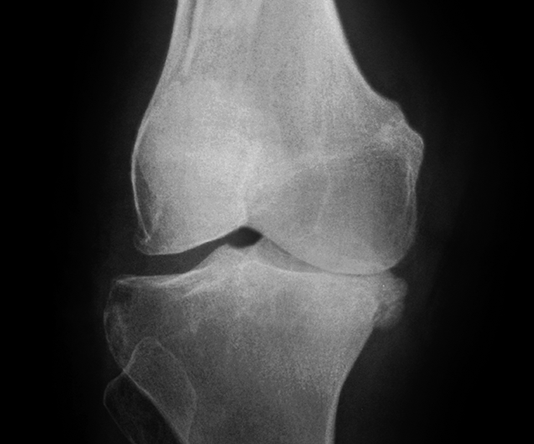

Hình ảnh của khớp gối trên phim X-quang: Khe khớp hẹp rõ, nhiều gai xương kích thước vừa, đặc xương dưới sụn, đầu xương có thể bị biến dạng.

Thoái hóa khớp gối tiến triển đến giai đoạn 3

Thoái hóa khớp gối tiến triển đến giai đoạn 3 thì bệnh nhân sẽ càng cảm nhận rõ những cơn đau tại khớp gối. Các lớp sụn khớp bao bọc các đầu xương bị bào mòn nhiều và khoảng không gian giữa các đầu xương bị thu hẹp thấy rõ. Khả năng đi bộ của người bệnh giảm, đi, đứng, ngồi xổm, lên xuống cầu thang cũng thấy đau. Tình trạng cứng khớp vào buổi sáng cũng xảy ra thường xuyên hơn kèm theo các đợt viêm khớp gối (sưng, đau, tràn dịch) hoặc có biểu hiện vẹo khớp gối.